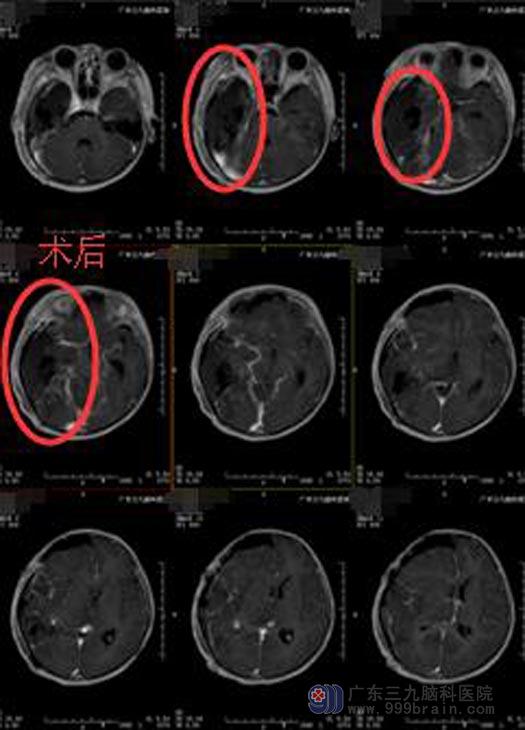

小瑜的病情重,年纪小,需尽快手术治疗,她的父母知晓病情后,同意在全麻下行“右侧颞枕岛叶基底节区多发占位病变切除术”。术中见肿瘤组织呈灰褐色,质软,边界不清,血供丰富,显微镜下分块全切肿瘤,手术过程顺利;术后小瑜神志清醒,应答正确,肢体活动正常,未见癫痫发作症状,顺利出院,等待后续的进一步治疗。